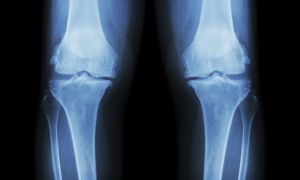

There are actually many systems working together to keep us standing upright. Balancing effectively takes our eyes, ears (vestibular system), and peripheral sensory system (skin receptors of pressure and touch) as well as our neuromuscular connections (the nerve pathways between our brains and muscles, tendons, ligaments, and joints). Our brains are able to coordinate these signals to determine where our limbs are in space and the speed and direction of their movement.